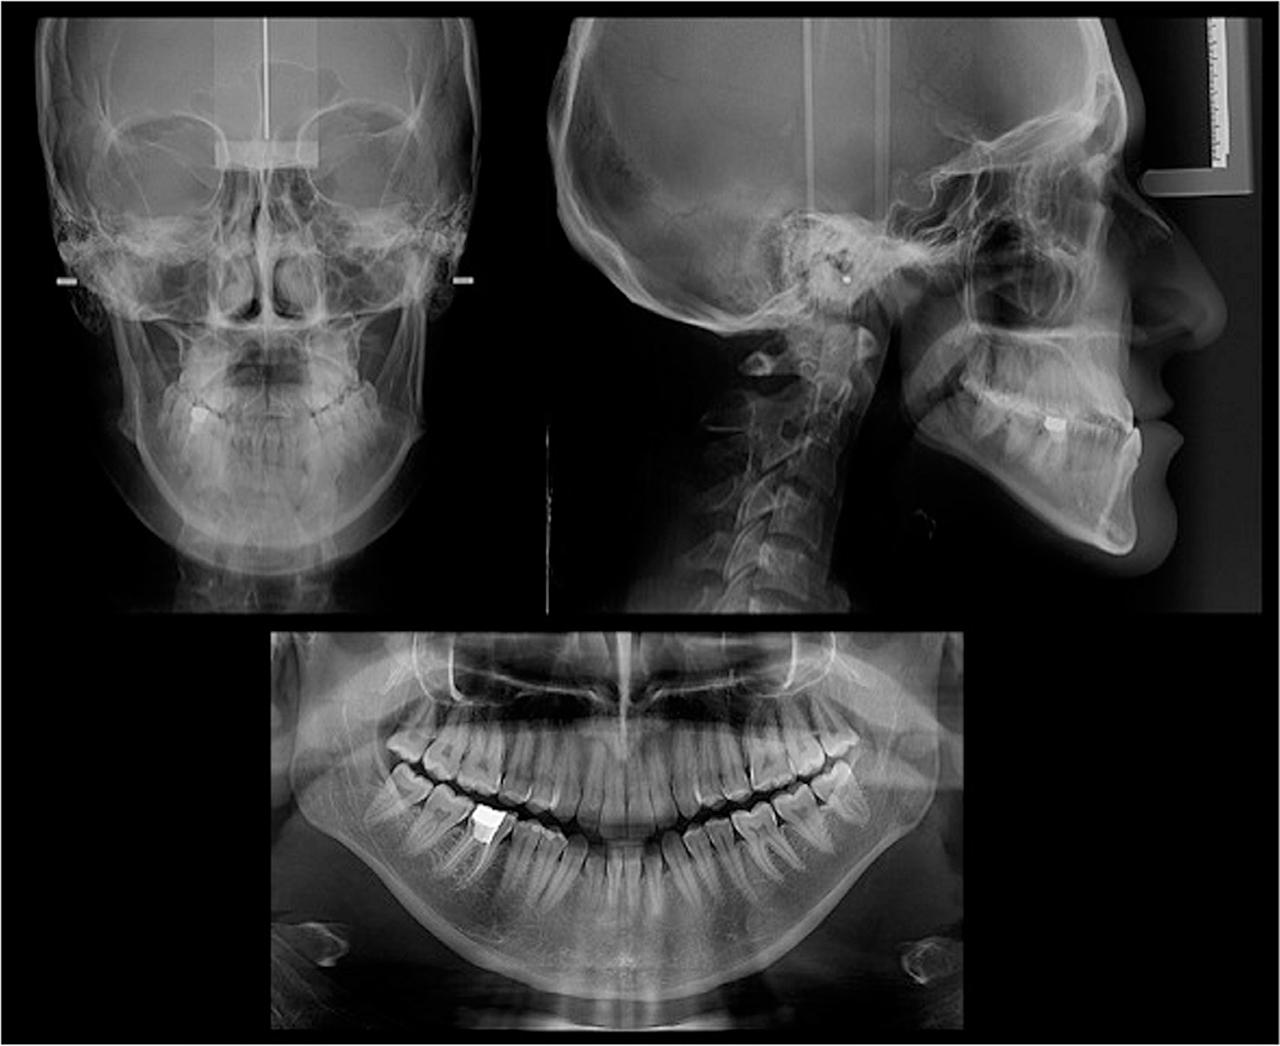

Figure 3

Pre-treatment posteroanterior cephalometric, lateral cephalometric and panoramic radiographs.

Caucasian adult female cephalometric normal values5 revealed a skeletal Class III relationship (ANB = −3.1°, Wits Appraisal = −11.3 mm) highlighted by maxillary retrusion (SNA = 76.9°). The vertical dimension indicated a hyperdivergent growth pattern (FMA = 31.7°) (Table I, Fig. 3). The upper incisor inclination was within the normal range (U1-NA = 24.1°) but the lower incisor inclination was reduced (L1-NB = 19.3°). A postero-anterior cephalometric analysis showed that the maxillary width (JR-JL) was 63.4 mm, and the inter-antegonial notch width (AG-GA) was 86.2 mm, producing a maxillo-mandibular differential of 22.8 mm (Fig. 3). According to the Ricketts/RMO analysis, the maxillo-mandibular transverse differential was 3.2 greater than the Rocky Mountain normal value (the maxillo-mandibular transverse differential index was 3.2).6